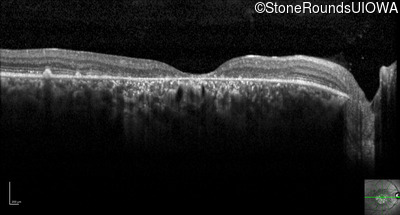

Optical Coherence Tomography - Right -

20/150 sc

Exemplar / OCT Stack